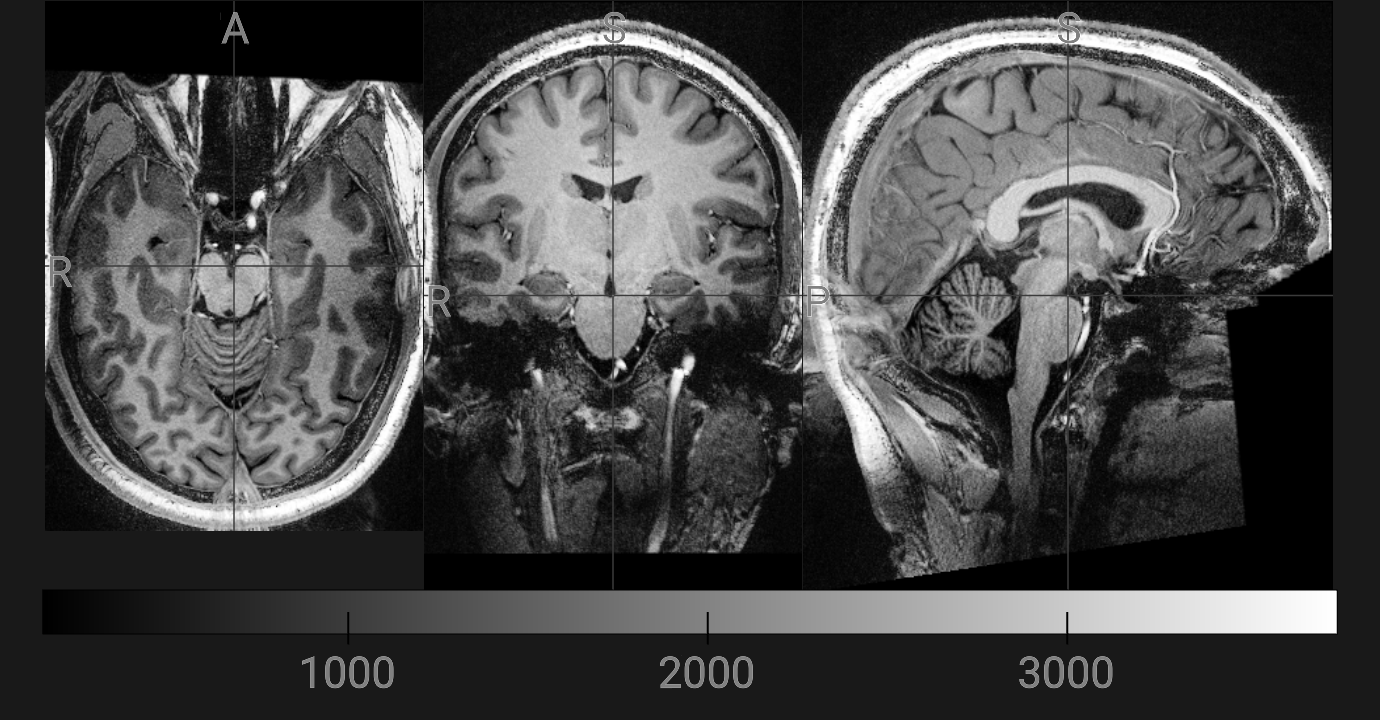

🖼️ Viewing mp2rage.nii.gz

We will now open the mp2rage.nii.gz file. This is the patient’s T1-weighted MRI scan that FreeSurfer will change into its own format.

- 🎛️ We display it in grayscale so brain tissue boundaries are clear

- 📐 Brightness/contrast is automatically adjusted (ignores empty space and extreme values)

- ➕ Crosshairs help you line up the same point across axial, coronal, and sagittal slices

- 🧭 The viewer lets you scroll through slices and explore the brain interactively